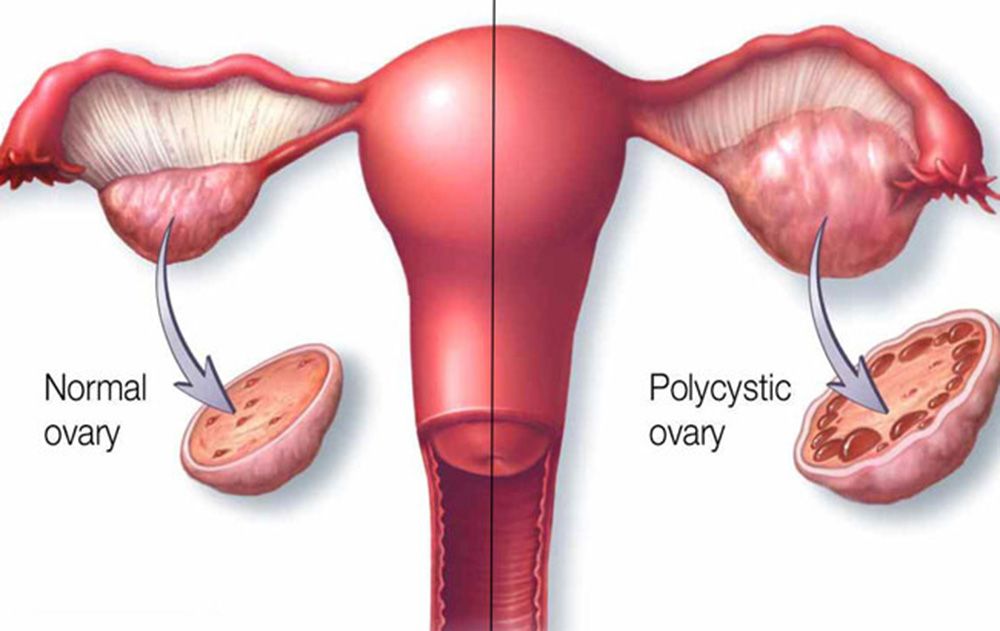

قیمت: 45٬000 تومان - دسته بندی فایل: پاورپوینتدانلود پاورپوینت شناخت کیست فولیکولی تخمدان

خرید پاورپوینت حرفه ای با موضوع شناخت کیست فولیکولی تخمدان با قیمت استثنایی از لوکس فایل